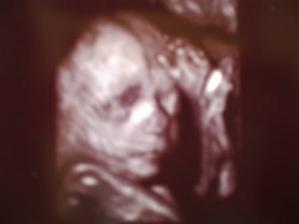

ovulace dorazila v prosinci,ale nic, přišla mrcha , další ovu 26. DC, poté 11 DPO pozitivní test , tj.5.2.09, nádhera